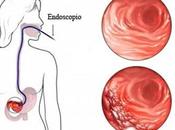

Chronic Gastritis – Causes, Symptoms, Ayurvedic Treatment, Herbal Remedies,...

INTRODUCTION OF THE DISEASE Chronic Gastritis is defined as the inflammation of the lining of the stomach. The stomach lining contains certain glands that... Read more